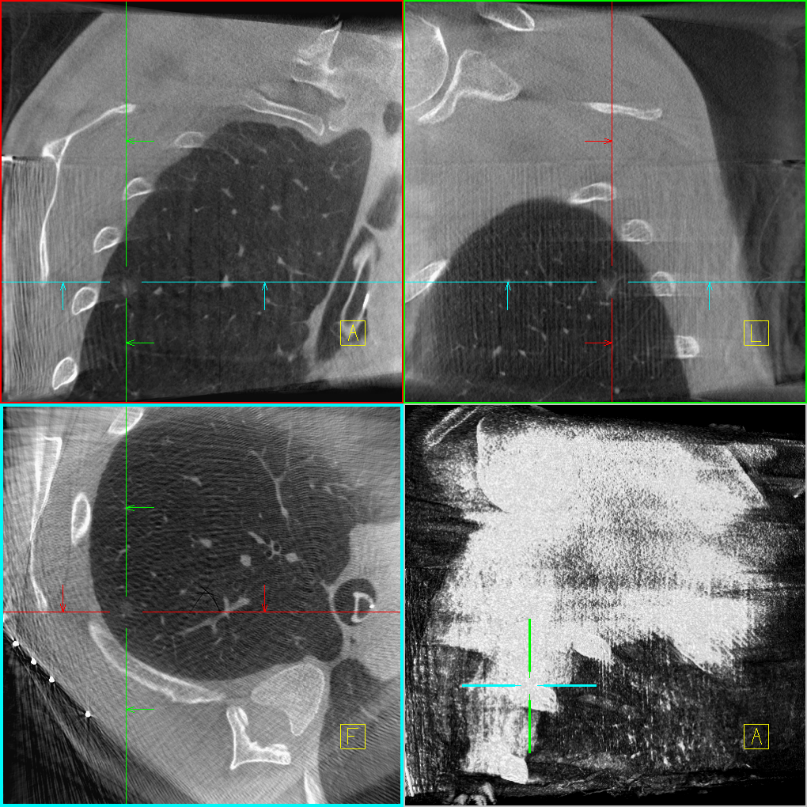

术前胸部CT

经过我院马海涛主任治疗团队评估病情后,决定为吴先生在全麻下行右上肺肺段切除术。因为吴先生右上肺的结节较小(约8mm),位于右上肺后段,马海涛主任治疗团队决定在行Cios Spin移动式C臂引导下激光导航定位肺结节+VATS肺手术,以快速精准地切除病灶。